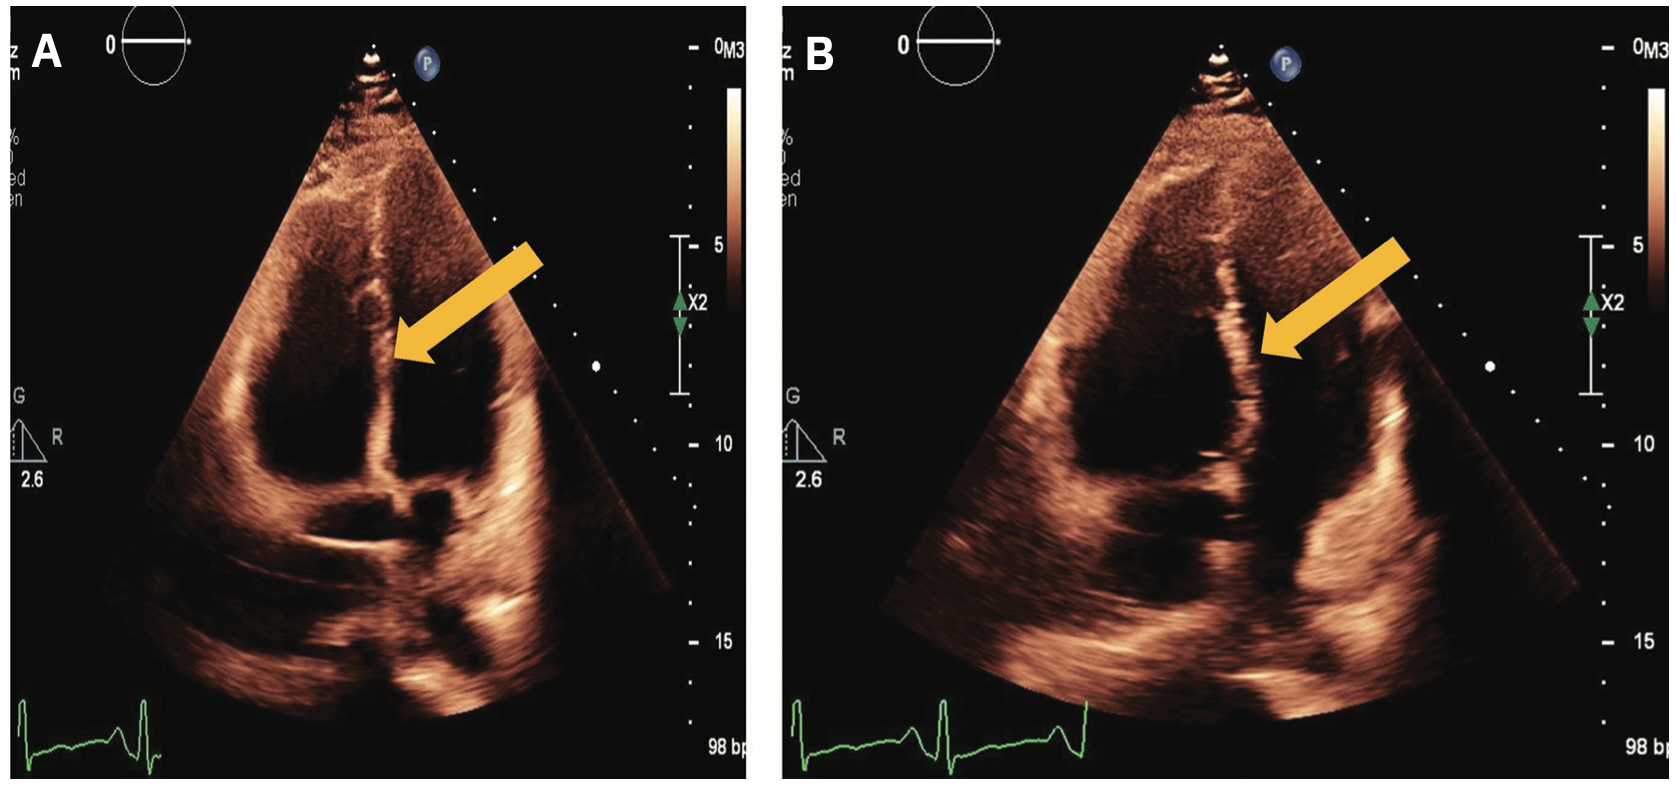

The patient’s subsequent transthoracic echocardiogram (TTE) demonstrated McConnell’s sign, a distinct feature of acute submassive PE. It is a pattern of RV dysfunction, with akinesia of the mid-free wall and hypercontractility of the apical wall.1 The TTE also revealed systolic flattening of the interventricular septum consistent with RV pressure overload, moderate dilation of the RV, and moderate-to-severe reduction in systolic RV function (Figure 2).